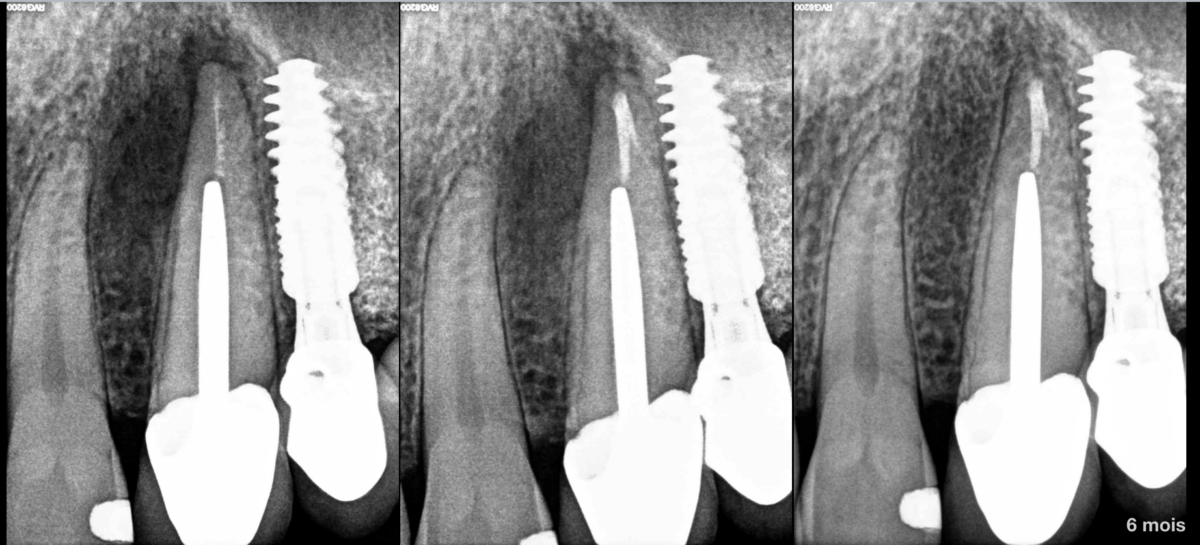

📚 𝐋𝐚 𝐥𝐢𝐭𝐭𝐞́𝐫𝐚𝐭𝐮𝐫𝐞 𝐧𝐞 𝐫𝐚𝐩𝐩𝐨𝐫𝐭𝐞 𝐝’𝐚𝐢𝐥𝐥𝐞𝐮𝐫𝐬 𝐩𝐚𝐬 𝐝𝐞 𝐝𝐢𝐟𝐟𝐞́𝐫𝐞𝐧𝐜𝐞 𝐝𝐞 𝐫𝐞́𝐬𝐮𝐥𝐭𝐚𝐭𝐬 𝐞𝐧𝐭𝐫𝐞 𝐥𝐞𝐬 𝐞𝐱𝐭𝐫𝐚𝐜𝐭𝐢𝐨𝐧𝐬-𝐢𝐦𝐩𝐥𝐚𝐧𝐭𝐚𝐭𝐢𝐨𝐧𝐬 𝐢𝐦𝐦𝐞́𝐝𝐢𝐚𝐭𝐞𝐬, 𝐞𝐟𝐟𝐞𝐜𝐭𝐮𝐞́𝐞𝐬 𝐬𝐮𝐫 𝐬𝐞𝐜𝐭𝐞𝐮𝐫 𝐚𝐯𝐞𝐜 𝐥𝐞́𝐬𝐢𝐨𝐧 𝐚𝐩𝐢𝐜𝐚𝐥𝐞 𝐨𝐮 𝐧𝐨𝐧.